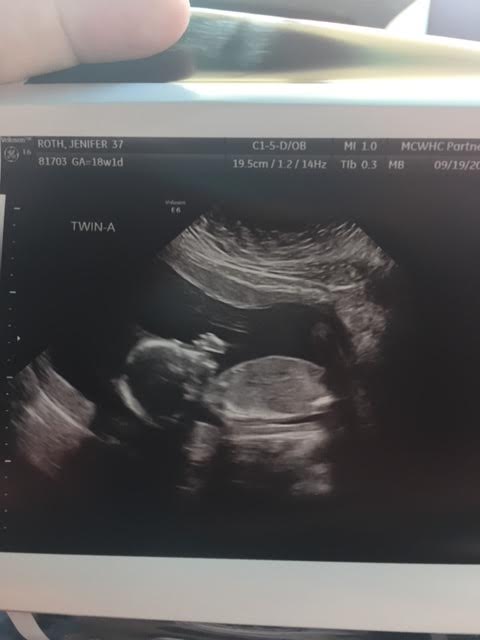

Ultrasound Photos at 18 Weeks Pregnant With Twins